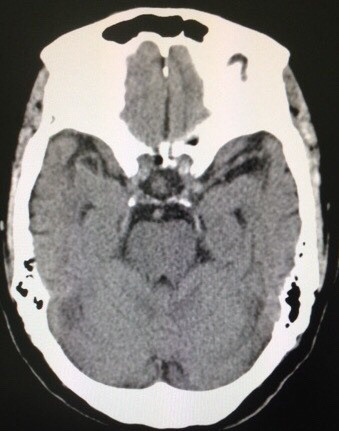

2017/01/13 『治療抵抗性』レビー小体型認知症の正体

そう、レビーオンリーじゃないだろうと言うこと。いよいよ、頭部CTをオーダー。

冠状断(脳を顔面方向から)透明中隔腔を認めます。確かに両側で

海馬は萎縮していますが・・・。トンデモもなく、重要な所見があります。

下記をご覧ください。

水平断(頭のてっぺんから)脳のシワ(脳溝)が細くて、目立ちませんよね。矢状断(頭を真横から)アタマのてっぺんにはやはり脳溝が目立ちません。さて・・・所沢の有志諸氏、この患者さんはナニを合併していたか、わかりましたか❓

答えは拙著194ページを‼️

冠状断(脳を顔面方向から)透明中隔腔を認めます。確かに両側で海馬は萎縮していますが・・・。トンデモもなく、重要な所見があります。